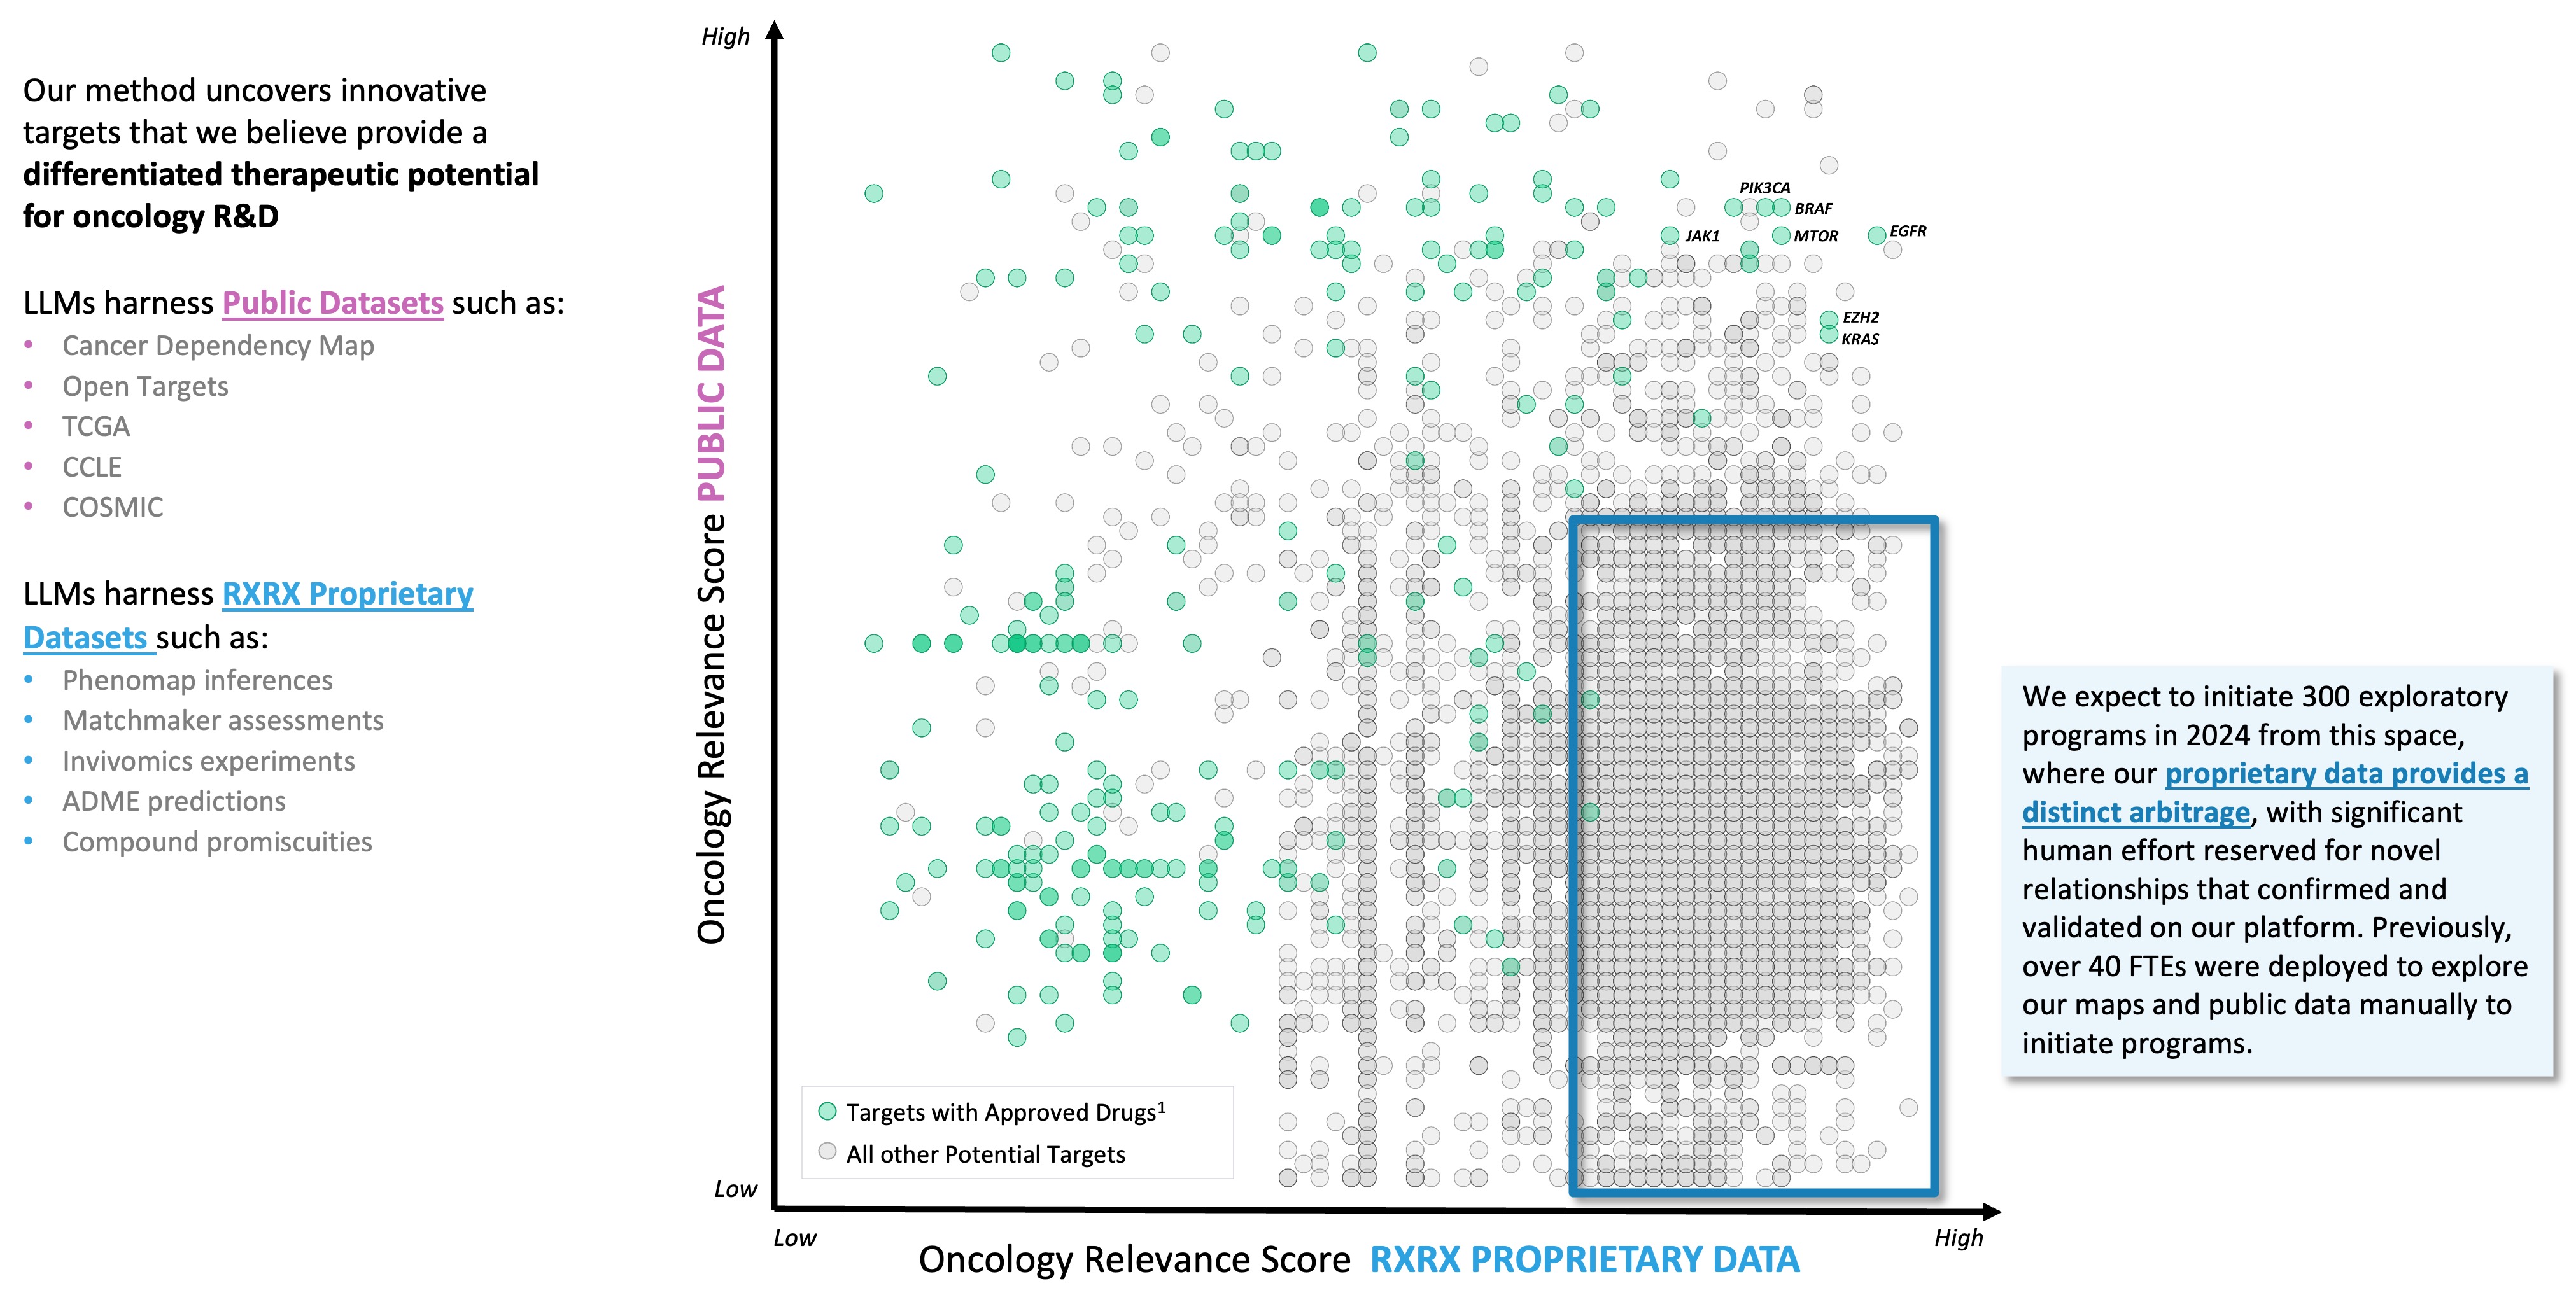

•Deployed large language models (LLMs) to map scientific literature in conjunction with our internally derived proprietary maps for the purpose of autonomously identifying novel opportunities in areas of unmet need

•Deployed Phenom-1, a vision transformer utilizing hundreds of millions of parameters trained on billions of biological images from our proprietary data, which we believe to be the world’s largest phenomics foundation model at this time

•Deployed new digital chemistry tools to predict the ligand-protein interactions for approximately 36 billion compounds in the Enamine REAL Space, reported to be the largest synthesizable chemical library

Figure 1. A simple formula is used across technology industries to map and navigate complex systems. First, high-dimensional data is generated, aggregated and organized to create digital representations. Then, AI/ML algorithms make predictions about that system that can be tested in reality. The result is a virtuous cycle of learning and iteration.

At Recursion, we are pioneering the integration of innovations across biology, chemistry, automation, data science and engineering to industrialize drug discovery in a full-stack solution across dozens of key workflows and processes critical in discovering and developing a drug. For example, by combining advances in high content microscopy with arrayed CRISPR genome editing techniques, we can rigorously profile massive, high-dimensional biological and chemical perturbation libraries in multiple human cellular contexts to create digital ‘maps’ of human biology. Leveraging advances in scaled computation, we can conduct massive virtual screens to predict the protein targets for billions of chemical compounds. Similarly, data generated from our automated DMPK module and InVivomics platform enables us to predict ADME properties and identify toxicity signals, respectively, significantly faster than traditional methods. We believe that by harnessing advances in technology to industrialize drug discovery, we can derive novel biological insights not previously described by scientific researchers, reduce the effects of human bias inherent in discovery biology and reduce translational risk at the program outset.